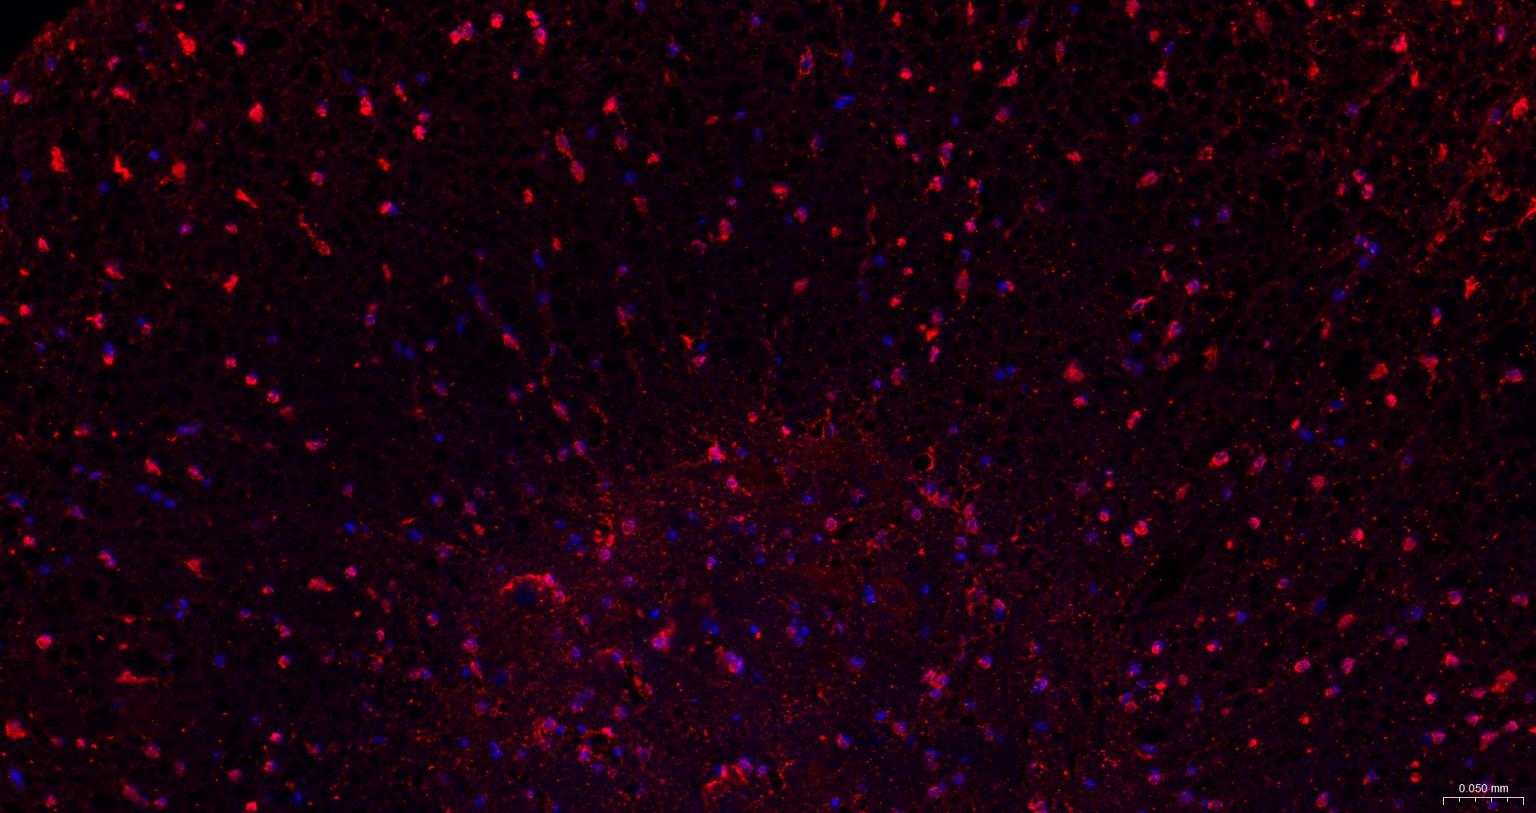

| IF | Human, Mouse, Rat | 1:100-500 |